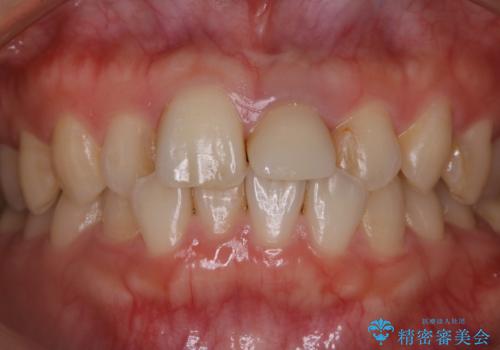

インビザラインのアタッチメントをつける前にPMTC

- インビザラインでの矯正治療中で、アタッチメントの設定前にきれな状態にしたいとのことでした。PMTC30分コースを行いました。

マウスピース矯正インビザライン治療では、歯の表面にアタッチメントという突起を設定します。(アタッチメントは歯の動きを効率的に移動するためのものです)

アタッチメントの設定時に、プラークや歯石・着色がついていると精密に付かないことや、外れやすくなることがあります。

PMTCを行い、専門的な機械でしっかりと汚れを除去してからアタッチメントの設定をすることがおススメです。